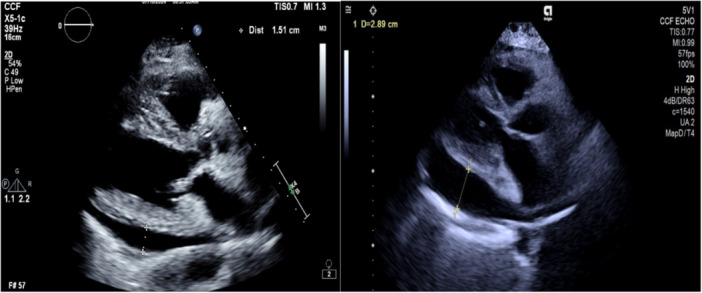

肺动脉高压(PAH)是一种以小肺动脉进行性重塑为特征的疾病,可导致肺血管阻力增加、右心室衰竭和过早死亡(1-2)。在过去的30年里,PAH的治疗取得了重大进展,包括最近批准的sotaterept,这是一种一流的融合蛋白,可作为激活素和生长分化因子的配体陷阱,这些因子是转化生长因子β (TGF-β)超家族的关键参与者(3-4)。sotaterept通过6分钟步行距离和世界卫生组织(WHO)功能分级来评估,可以提高运动能力,降低肺血管阻力和NT-pro脑钠肽,提高简化的French风险评分,同时延长死亡或非致命性临床恶化的时间(3)。在第7届世界肺动脉高压研讨会上,建议将索特西普作为一种选择,用于中度或高风险的PAH患者,尽管联合使用至少一种内皮素受体拮抗剂和磷酸二酯酶5型抑制剂,但仍未达到低风险。索特西普在PAH患者中的STELLAR研究证实了该药物对接受背景治疗的患者的疗效(3)。事实上,34%的患者接受双重治疗60%的患者接受三重治疗。有趣的是,40%的患者接受前列环素输注治疗(3)。对恒星研究的事后分析显示,双重或三重背景多环芳烃治疗以及基线时接受前列环素输注的患者都有有益的效果(1,5)。目前尚不清楚在其他多环芳烃治疗中加入索特塞普是否会产生意想不到的并发症。有可能通过重新平衡肺循环中的增殖/抗增殖作用,其他治疗多环芳烃的效果可能会变得过度,特别是当高剂量外注射前列环素时。这种现象可能表现为前列环素过量的典型特征,包括副作用增强和高心排血量心力衰竭。在此,我们描述了一位接受三联PAH特异性治疗的PAH患者,他在开始使用索特塞普后出现大量心包积液和高心排血量心力衰竭。

Pulmonary arterial hypertension (PAH) is a disorder characterized by progressive remodeling of small pulmonary arteries, leading to increased pulmonary vascular resistance, right ventricular failure and premature death (1-2). Over the past 30 years, significant advancements have been made in the treatment of PAH, including the recent approval of sotatercept, a first-in-class fusion protein that acts as a ligand trap for activins and growth differentiation factors, which are key players in the transforming growth factor β (TGF-β) superfamily (3-4). Sotatercept improves exercise capacity, as assessed by 6-min walk distance and World Health Organization (WHO) functional class, reduces pulmonary vascular resistance and NT-pro brain natriuretic peptide, and improves the simplified French risk score while extending the time to death or nonfatal clinical worsening (3). The 7th World Symposium in pulmonary hypertension recommends the addition of sotatercept as an option in PAH patients who have not achieved low risk despite combination therapy with at least an endothelin receptor antagonist and phosphodiesterase type-5 inhibitor, in intermediate or high-risk patients. The STELLAR study of sotatercept in PAH patients demonstrated the efficacy of this medication in patients receiving background therapy (3). In fact, 34% of the patients were on double and 60% of the patients on triple therapy. Interestingly 40% were on prostacyclin infusion therapy (3). Post-hoc analysis of the stellar study showed a beneficial effect for those on double or triple background PAH therapy as well as those receiving prostacyclin infusion at baseline (1,5). It remains unclear if the addition of sotatercept to other PAH treatments may have unexpected complications. It is possible that by rebalancing the proliferative/antiproliferative effects in the pulmonary circulation, the effect of other treatments for PAH may become excessive, particularly when parenteral prostacyclin is used at high doses. This phenomenon may manifest with the typical characteristics of prostacyclin overdose, including enhanced side effects and high cardiac output heart failure. Hereby we describe a patient with PAH on triple PAH-specific therapy, who after the initiation of sotatercept developed a large pericardial effusion and high cardiac output heart failure.